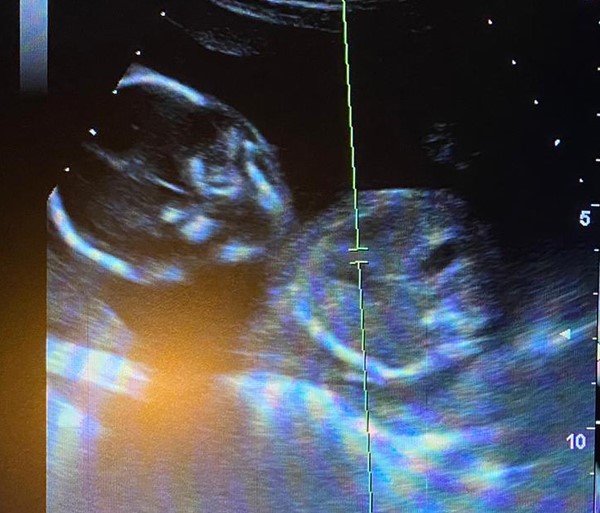

Heartbeat of Miami operates four pregnancy resource medical clinics in Miami-Dade County, with a sonographer working at each facility. Jashley visited the North Miami center, and during her appointment, she and her boyfriend were able to see their six-week-old unborn child on the ultrasound. They also heard their little one’s heartbeat. These experiences caused them to change their minds about abortion.

Later, when Jashley was 24 weeks along, she returned to the clinic for a 3D/4D ultrasound, which revealed a baby girl. Jashley’s child is due in April, Avila said.